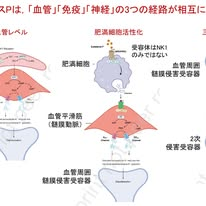

では,なぜサブスタンスPで片頭痛が起こるのでしょうか.この点を理解するうえで重要なのが図1の4つで,「血管」「免疫」「神経」の3つの経路が相互に作用することが示されています.まず血管のレベルでは,サブスタンスPが血管内皮のNK1受容体に作用し,一酸化窒素の産生を介してcGMPシグナルを活性化し,カリウムチャネルを開口させることで髄膜血管を拡張させます.この血管拡張は血管壁の伸展や周囲のイオン環境の変化を引き起こし,血管周囲に存在する侵害受容器の閾値を低下させ,発火しやすい状態を作ります.

次に免疫のレベルでは,サブスタンスPが肥満細胞を活性化し,ヒスタミンなどの炎症性メディエーターを放出させます.これにより神経原性炎症が生じ,血管拡張がさらに増強されるとともに,侵害受容器の感受性が一層高まります.ここで重要なのは,この過程がNK1受容体だけでなくMRGPRX2など「複数の受容体を介して起こる可能性」がある点で,サブスタンスPの作用が単一経路ではないことを示しています.

加えて神経のレベルでは,サブスタンスPが三叉神経終末や三叉神経脊髄路核に作用して神経の興奮性を高め,痛みの信号を中枢へと増幅して伝達します.これはサブスタンスPの中枢への直接作用というより,まず髄膜での末梢メカニズムが起点となり,その結果として中枢の痛覚ネットワークが動員されると考えられます.このようにサブスタンスPは単に血管を拡張させるだけではなく,「血管」「免疫」「神経」を同時に動かすハブとして働き,それらが重なり合うことで片頭痛発作が成立するという統合モデルが提唱されています.